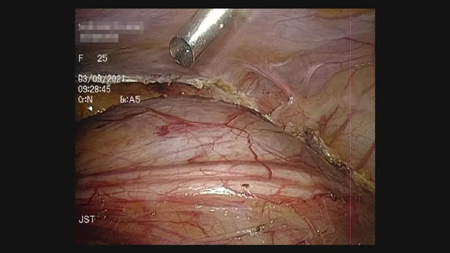

手术当天由毕敬涛副主任医师、赵景明主任医师和蔡轩主治医师主刀完成,术中探查发现患者存在第二腹腔,其表面可见被顶起的重复输尿管畸形,而腔内的重复肠管为类结肠结构并一直延续到盆底,子宫及附件结构已被挤压到了左侧盆壁。术中小心保护输尿管结构与周围重要血管和神经,充分游离重复肠管并在盆底处将其离断。关闭腹腔后再改变患者体位为侧卧位,沿处理臀部窦道,贯通至盆腔内。经过近数小时的艰苦奋战,按照既定计划,三位专家成功将完整的重复消化道移出腹腔!

被顶起的重复输尿管畸形

沿处理臀部窦道,贯通至盆腔内